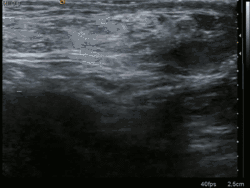

Ultrasound image of inguinal hernia. Moving intestines in the inguinal canal with respiration.